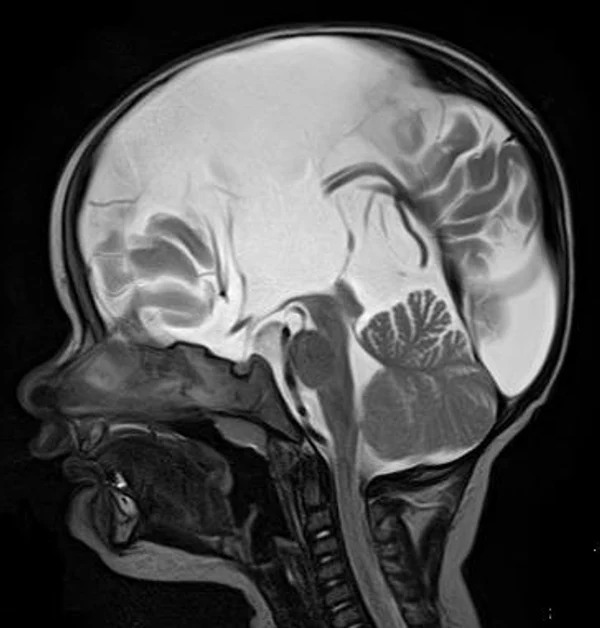

кисты, аномалии Денди-Уокера и др.Операции при внутричерепных кистах. В основном встречаются арахноидальные кисты различных локализаций и кисты сосудистых сплетений боковых желудочков. Пациентам с врождёнными кистами операции проводятся в следующих ситуациях: увеличении объема кисты в динамике, наличии клинических проявлений, компрессии и дислокации мозговых структур, наличии окклюзии ликворных путей. Нами используются 2 способа хирургического лечения кист: эндоскопическая перфорация стенок кист и открытая резекция кист. Открытая резекция кист проводится при ретроцеребеллярных арахноидальных кистах (рис. 2), при арахноидальных кистах межполушарной щели при отсутствии непосредственного контакта их стенок со стенками расширенных желудочков головного мозга и повторного увеличения кист средней черепной ямки после эндоскопической кисто-цистерностомии. Техника операции заключается в проведение краниотомии и максимальном иссечении стенок кист с созданием широкого сообщения кист с субарахноидальным пространством. Эндоскопические операции проводятся при арахноидальных кистах межножковой и пинеальной цистерн, арахноидальных кистах межполушарной щели при тесном контакте их стенок со стенками расширенной желудочковой системы (рис. 3), первично при арахноидальных кистах средней черепной ямки, а также при кистах сосудистых сплетений боковых желудочков. При арахноидальных кистах межножковой цистерны эндоскопически проводится перфорация стенок кисты, сообщая ее с просветом III желудочка и межножковой цистерной – эндоскопическая вентрикуло-кисто-цистерностомия (рис. 4). При арахноидальных кистах пинеальной цистерны проводится перфорация кисты в передне-верхних её отделах с созданием сообщения полости кисты с просветом III желудочка – эндоскопическая кисто-вентрикулостомия. С целью предотвращения облитерации сформированного отверстия иногда в полость кисты под контролем эндоскопа вводится стент перфорированный на протяжении (рис. 5, 6). Эндоскопическая кисто-цистерностомия выполняется при арахноидальных кистах средней черепной ямки. При этом создается широкое сообщение кисты с базальными цистернами. При кистах сосудистых сплетений боковых желудочков проводится их вскрытие в просвет боковых желудочков – эндоскопическая кисто-вентрикулостомия. При множественных кистах проводится их хирургическое сообщение между собой – интеркистосмия